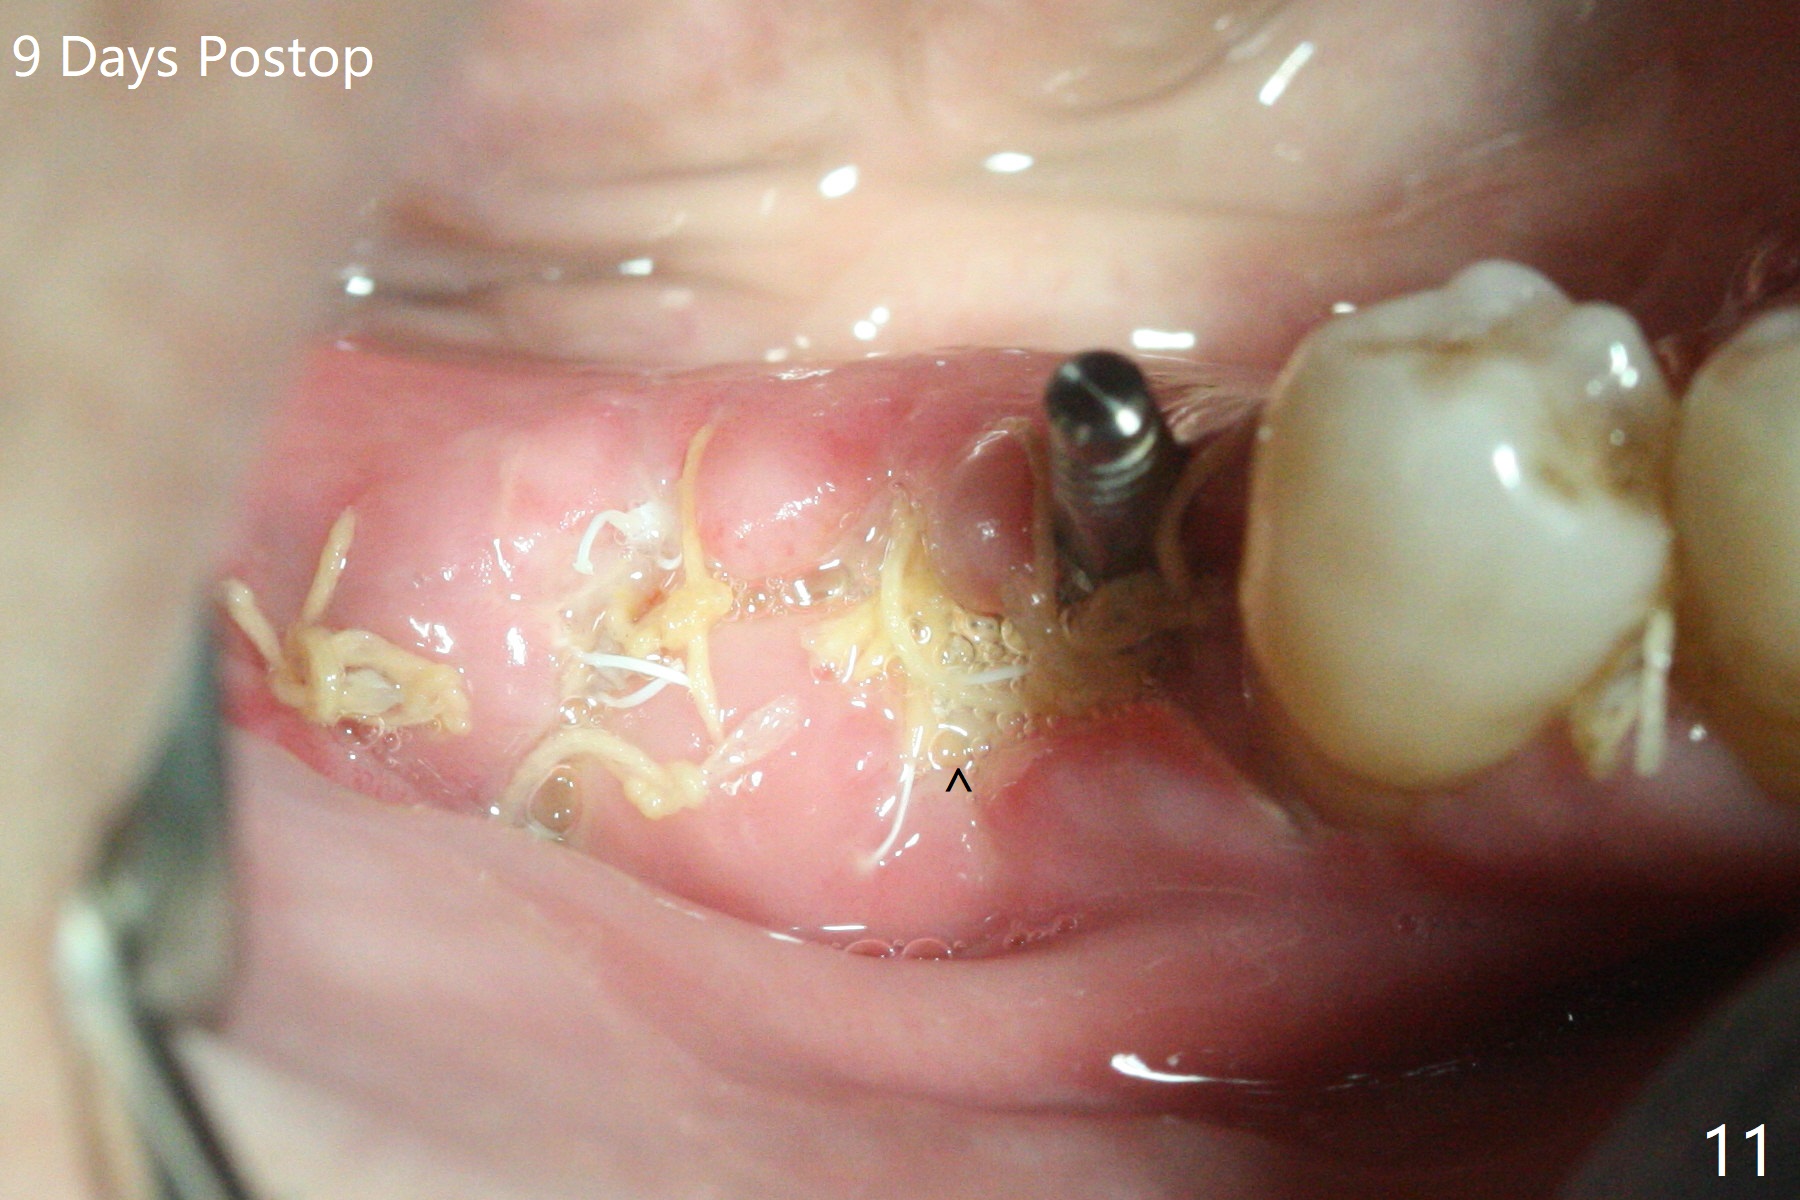

The implant at #30 was also buccally placed (Fig.6,7) and should be corrected in the same manner (Fig.7 green). Due to the bone being harder in the molar region, a smaller and shorter implant (4x11 mm vs. 5x13 mm) shifts slightly buccally while being placed (Fig.8,9). Since primary stability is lower (<20 Ncm vs. 35 Ncm associated with the implant #29), an abutment is not placed, which may be favorable to healing, but it is difficult to achieve primary closure. After bone graft (Fig.9 *) and 2 layers of PRF, Cytoplast is placed. Cytoplast appears to be exposed buccally (Fig.10 <) and occlusally (Fig.11 ^) asymptomatic 9 days postop. Exposure of Cytoplast is more distinct without sign of infection 15 days postop (Fig.12). The patient returns with chief complaint of "foul smell" 7 weeks postop (coronavirus lockdown). Although the Cytoplast exposes more (Fig.13 (* exposed; @ unexposed)), the underlying gingiva remains healthy (Fig.14). While the bone height decreases at #29, the bone density at #30 increases 4.5 months postop (Fig.15). The gingiva heals. The implant at #30 is uncovered 6 months postop. The lingual plate has to be removed for the uncover, while the coronal end of the buccal one is missing. No bone graft is added. When the 4.5x4 mm healing abutment is removed 6.5 months postop, the buccal plate looks concave at #30 (Fig.16' *). The buccal plate looks thin at #29 with a cotton roll placed buccally (Fig.16 R). The lingual plate at #29 is coronal to the buccal one (Fig.17). The buccal gingiva at #29 is quite long (Fig.18). The coronal buccal plate appears to be missing (Fig.19 >), which will be watched. A 4.5x7.5(4) mm cemented abutment is torqued (Fig.20).